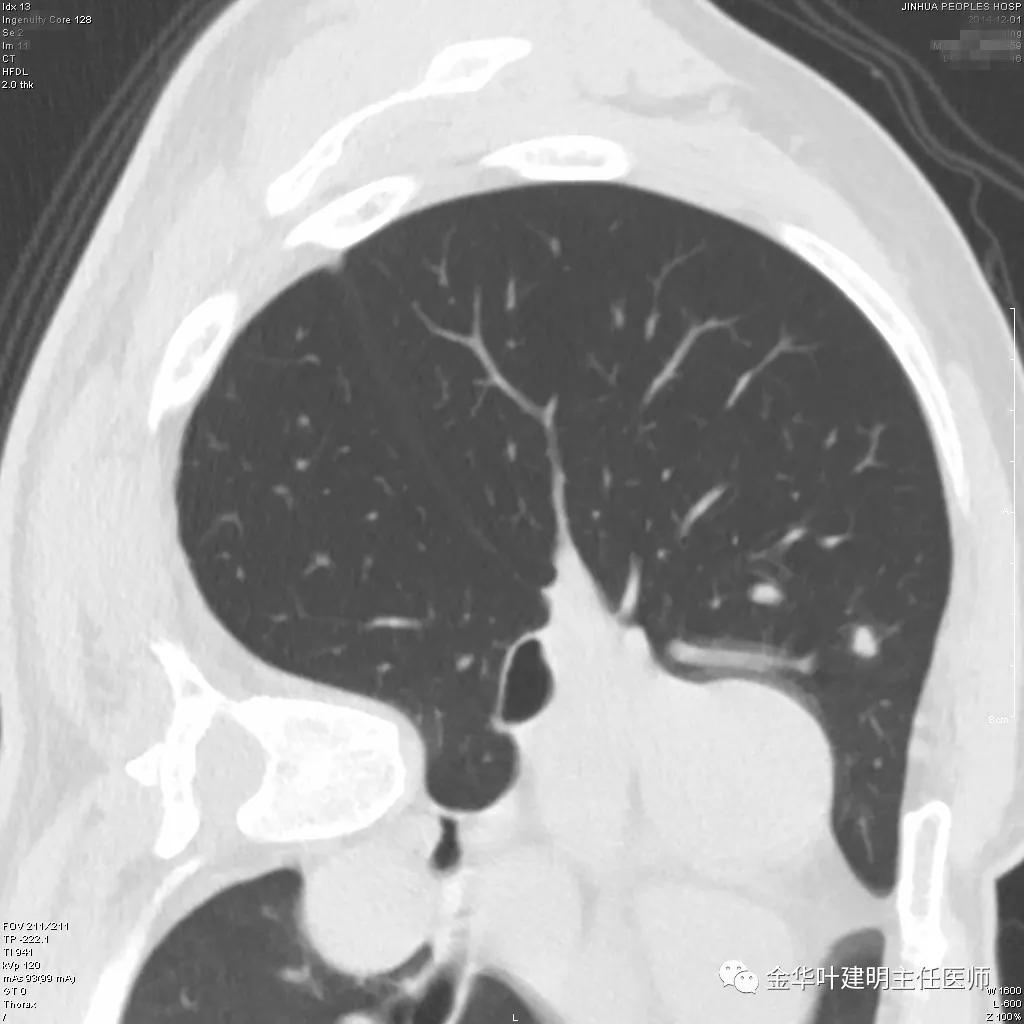

患者为48岁男性,检查发现左肺上叶实性结节,临床没有炎症表现,肿瘤指标不高,没有查过结核及隐球菌荚膜抗原试验或G试验、M试验等。我们先来看其前一个月时的平扫影像:

我们见左上实性病灶,主病灶旁有卫星灶,有血管进入,但也有贴边走行,边缘略显模糊,膨胀感与细毛刺不明显,收缩力也不明显。下面是其靶扫描的片子: